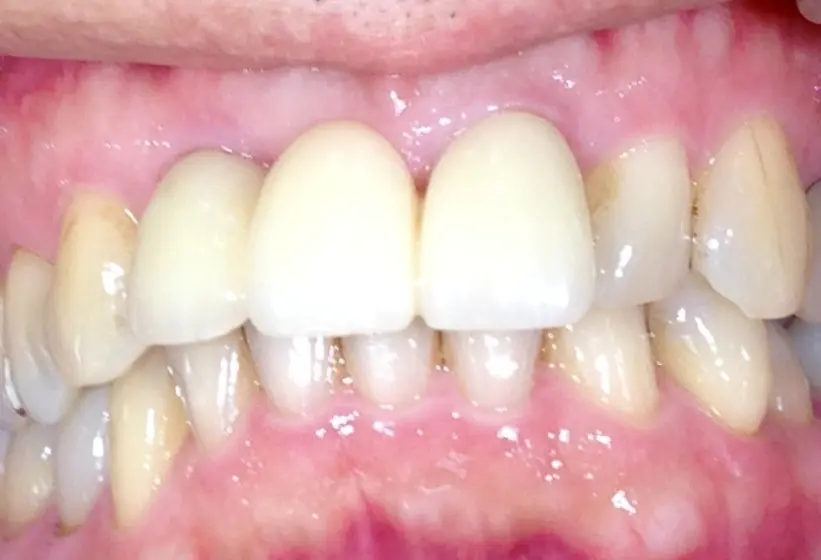

術後1年口腔内写真

ウミの出口もなくなり外科的処置の跡はほとんどなく、被せ物も天然歯と見分けつきません